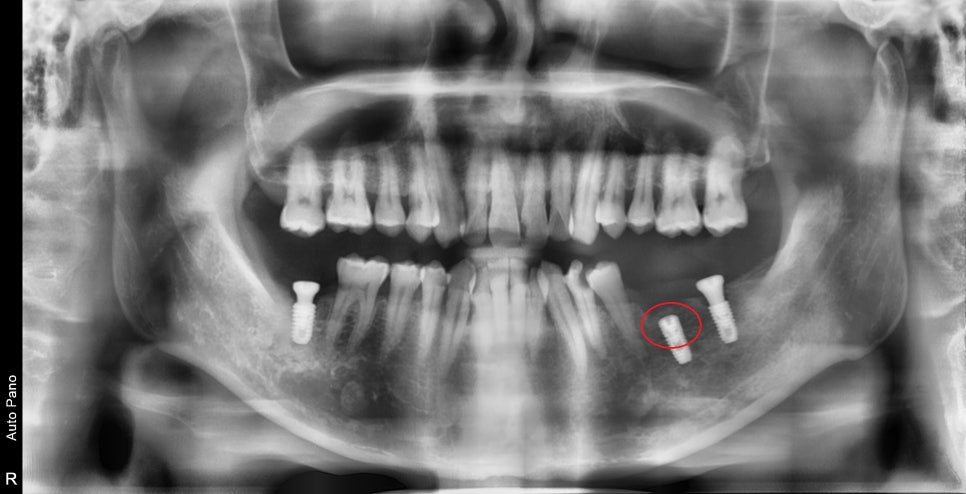

먼저 시간이 오래 걸리는 임플란트부터 심었습니다.

염증이 심했던 뿌리를 제거한 곳은 임플란트 식립과 동시에 뼈이식으로 같이 하고 잇몸 안에 묻어놓은 상태입니다.

이제 임플란트가 뼈와 붙는 기간 동안 주변 충치 치료를 시작합니다.

임플란트 본을 뜰 시기에 맞춰 많이 정출되어 있는 치아들을 의도적으로 신경치료 후 보철 치료까지 진행하였습니다.